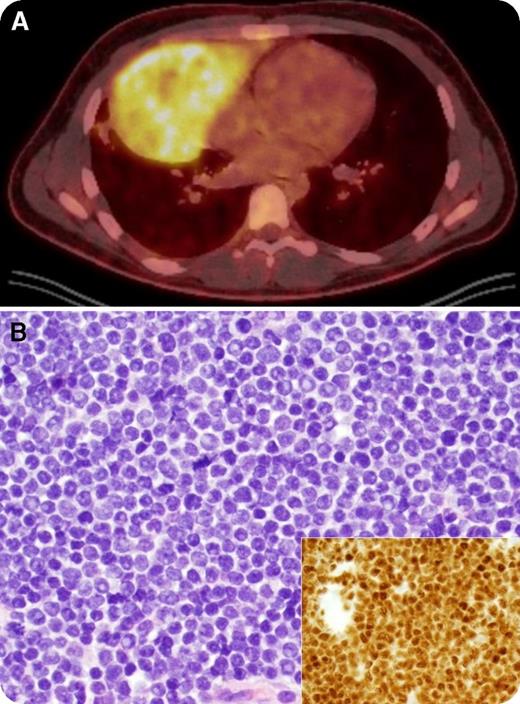

An 18-year-old man presented with a 2-month history of unintentional 23-kg weight loss, night sweats, and left-sided neck swelling. Physical examination revealed left supraclavicular lymphadenopathy. A complete blood count was within normal limits (white blood cells, 6.6 × 109/L) and a peripheral blood smear only identified a rare immature cell. Positron emission tomography showed a 16- × 9-cm hypermetabolic mediastinal mass mirroring the heart in the right hemithorax (panel A, “double-heart” sign) and extending into the neck. Biopsy of the mediastinal mass revealed a diffuse infiltrate of intermediate-sized T lymphoblasts with high nuclear-to-cytoplasmic ratio, fine chromatin, prominent nucleoli, and frequent mitotic figures (panel B; original magnification ×400; main panel, hematoxylin and eosin stain; inset, terminal deoxynucleotidyl transferase stain). The bone marrow was 50% involved, establishing a diagnosis of T-cell acute lymphoblastic leukemia (T-ALL). Cervical lymphadenopathy resolved completely on physical examination within 2 days of starting steroids as a component of AALL1231 and the patient achieved a complete remission after 1 cycle.

The differential diagnosis of a mediastinal mass in a young adult includes thymoma, T-ALL, large B-cell lymphoma, Hodgkin lymphoma, and germ cell tumors. T-ALL masses are often exquisitely sensitive to steroids; hence, empiric steroid treatment before biopsy may result in rapid resolution of the mass and inadequate or nondiagnostic biopsy specimens.